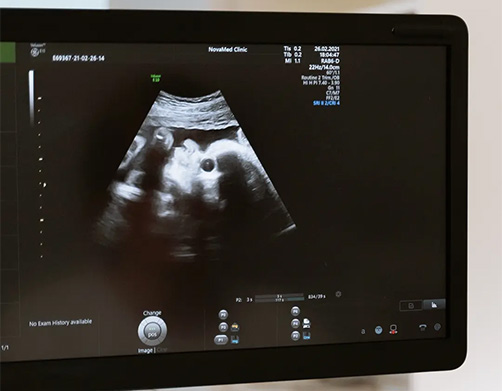

At 4d Baby Face Our Confirmation Scan is from 6 -12 weeks Just found out you’re pregnant? Let us help confirm your exciting news. Our Confirmation Scan is designed for women in the very early stages of pregnancy who would like reassurance that their pregnancy is progressing as expected.performed from 6weeks-11weeks

Recommended from: 6–11 weeks of pregnancy.